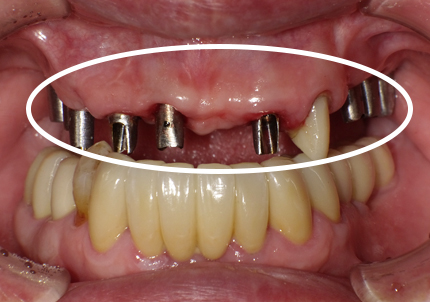

10. 上顎インプラントアバットメント装着 口腔内写真

11. ビスケットベイク(素焼き) 口腔内調整

【 口腔内にて歯冠長の最終調整 】